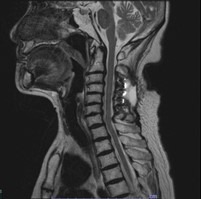

• 頚椎椎弓形成術

適応となる疾患

頚椎症性脊髄症、頚椎後縦靭帯骨化症など

神経を圧迫している骨成分をチタン製のプレートを用いて挙上させることにより、狭くなった脊柱管を拡大させます。手術創もなるべく小さく当院では本手術を行っております。

術前

術後